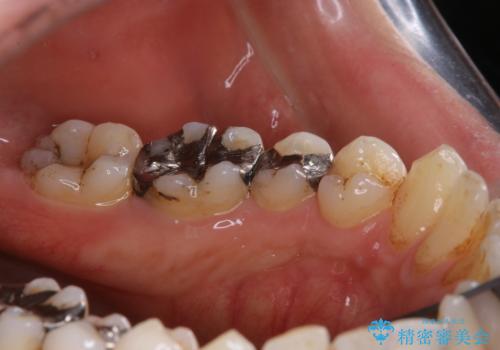

歯の表面に、茶色く色が残っている所がありますが、これは詰め物の変色によるものです。以前に、CR(コンポジットレジン)による虫歯治療がされています。

CRは経年的劣化や、着色してしまうことがあります。PMTCでクリーニングを行うと、古いCRが目立つことがあるため、気になる際は詰め替えを行います。

茶色くなっている部分が、着色なのか、劣化なのか、虫歯によるものなのかは判別が難しいことがあります。そのため、定期的にPMTCを行うことで状態の確認が的確に行えます。